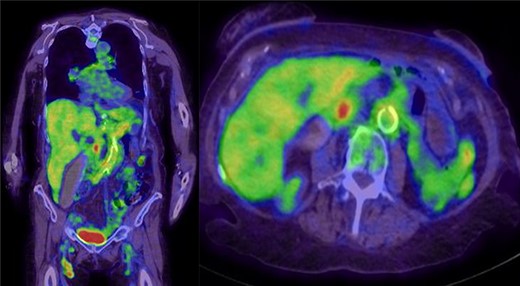

An endoscopic retrograde cholangiopancreatography (ERCP) was done with the intention of placing a stent to relieve biliary obstruction as well as provide an opportunity for brushings or biopsy. No obvious luminal malignant mass was visualized, and stents were unable to be placed due to complete CBD obstruction. Brushings taken at ERCP did not reveal any malignant cells. From here, a fluorodeoxyglucose positron emission tomography (FDG PET) scan was done. This showed focal uptake in the pancreatic head near the area of biliary amputation, as well as uptake in the thickened pancreas, arteries including the aorta and branching vascular uptake in the right lobe of the liver (Fig. 3). Again, an inflammatory disease such as IgG4-RD could account for this picture, but a primary neoplastic process around the head of the pancreas remained of concern.

PET-CT whole body—focal increased uptake in the pancreatic head near the region of biliary tree amputation; increased heterogeneous uptake in the pancreas and kidneys; branching uptake in the right liver lobe suggesting vasculitis; extensive thoracic and abdominal aortic uptake indicating arteritis; other findings included prominent nodes with uptake in mediastinum, bilateral inguinal and external iliac.